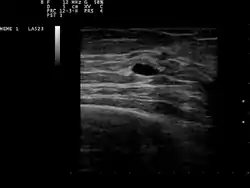

![]() تصوير بالموجات فوق الصوتية يظهر كيس صغير في الثدي. تصنيف وموارد خارجية: تصوير بالموجات فوق الصوتية يظهر كيس صغير في الثدي. تصنيف وموارد خارجية: | |

يمكن التأكد من وجود ورم ثديي في طبيعة الكيس عن طريق الفحص بالموجات فوق الصوتية، الشفط [6] (إزالة محتويات الكيس بواسطة الإبرة)، أو صورة الثدي الشعاعية(تصوير الثدي الشعاعي). الموجات فوق الصوتية يمكن أن تظهر أيضا إذا كان الكيس يحتوي على عقيدات صلبة، علامة على أن الآفة قد تكون محتملة التسرطن أو سرطانية. فحص السائل المرتشف من الكيس من قبل اختصاصي الباثولوجيا الخلوية (علم الأمراض الخلوي)قد يساعد أيضا في التشخيص. على وجه الخصوص، فإنه ينبغي أن ترسل العينة إلى المختبر لمعرفة إذا كانت ملطخة بالدماء.

وعادة ما يتم إعطاء صورة الثدي الإشعاعية التشخيصية للمرضى المشتبهين بأكياس الثدي، على الرغم من أنها لا تشتبه من السرطان. هذا النوع من صور الثدي الإشعاعية تسمح للطبيب بإمكانية إجراء صورة الثدي بالموجات فوق الصوتية في نفس الوقت، وهذا هو سبب تفضيلها في كثير من الأحيان عن صور الثدي الإشعاعي. تعتبر صور الثدي بالموجات فوق الصوتية الخيار الأفضل عند تشخيص أكياس الثدي لأنه 95-100٪ صحيحة، يقدم صورة واضحة عن ظهور الكيس و(بسيطة أو معقدة)، وأنه قد يميز أيضا بين الكتل الصلبة والأكياس المملوءة بسائل، والتي لا توفرها صورة الثدي الإشعاعية.[7] تتم صورة الثدي بالموجات فوق الصوتية بمساعدة جهاز طبي محمول باليد الذي يتم وضعه على الجلد، بعد أن تم وضع نوع خاص من السوائل على ذلك. تلتقط الأجهزة صدى من الموجات الصوتية المرسلة للثدي. وتنتقل هذه الأصداء إلى جهاز الكمبيوتر الذي يترجم إلى صورة.